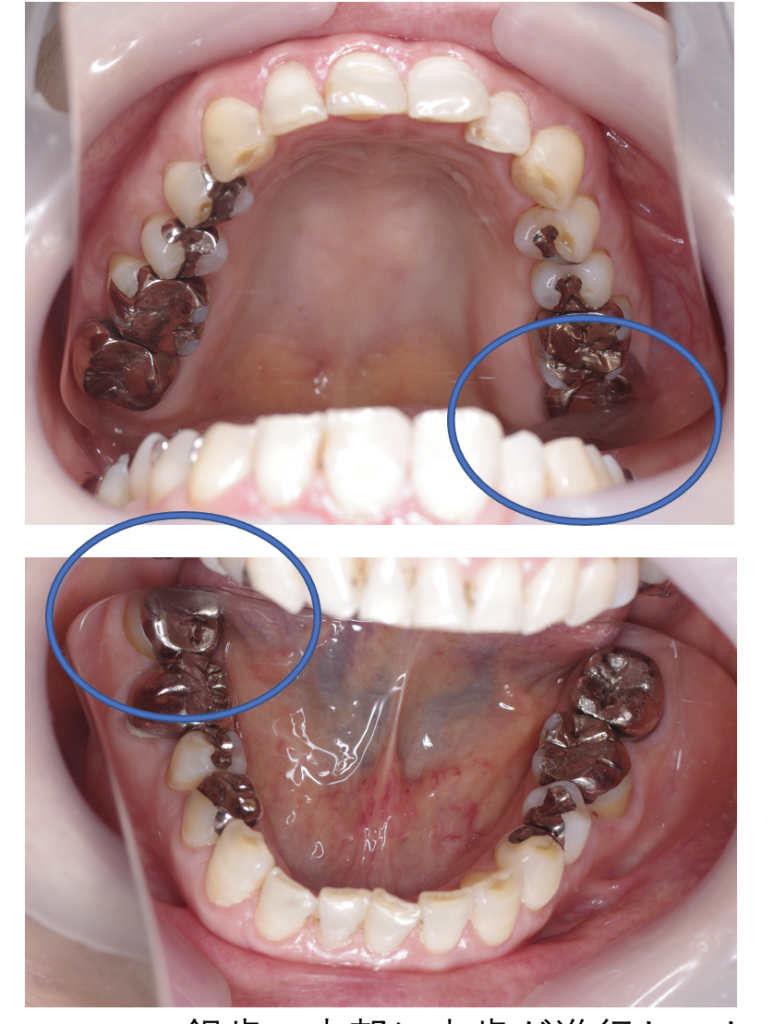

クラウンフルジルコニア

フルジルコニアCr 32 No.79

Before

After

| 治療方法 | フルジルコニアCr 虫歯などで失った歯質を天然歯と同じ色・質感のセラミックの一種であるジルコニア(人工ダイヤモンド)で補う治療法。 |

| 治療のデメリット | 変色がなく耐久性の高い治療ですが、歯周病や二次虫歯を予防するためには歯科医院での定期的なメインテナンスが大切です。 |

| 費用 | ¥89,000 |

| 通院回数 | 1ヶ月〜6ヶ月 |

| 備考 | 院長より 銀歯の内部に虫歯が進行してしまっていたケースです。中を開けて見てみると、外から想像するよりもはるかに虫歯が広がってしまっていました。残存歯質がかなり薄く弱くなってしまったので、ジルコニアで被せて守ってあげています。しっかりとした治療ができたので、まだまだ長く使っていけるでしょう。金属をなくすと、お口の中が明るくなりました。 |